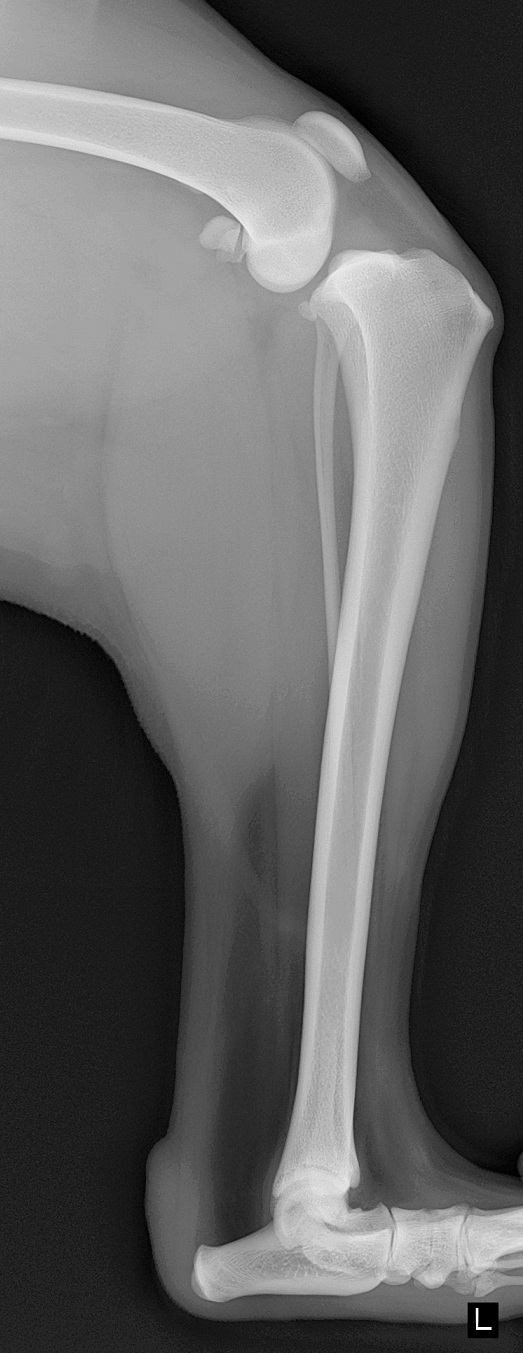

膝の安定性に重要な役割をしている前十字靭帯が断裂すると、下の写真のように大腿骨に対して脛骨の前方変位が起こります。カイちゃんは2年ほど前に右の前十字靭帯の断裂を起こしました。今回は、左の前十字靭帯を断裂しました。

カイちゃんはTPAが34°でしたので、TPLOを行いました。脛骨近位部を骨切りし、TPAを6°の角度にして特殊なプレートで固定します。TPAを6°前後に変更することで、脛骨の前方変位が起こらなくなり、膝の安定性が得られ早期に足を使うことが出来るようになります。

手術後側面像

手術後正面像